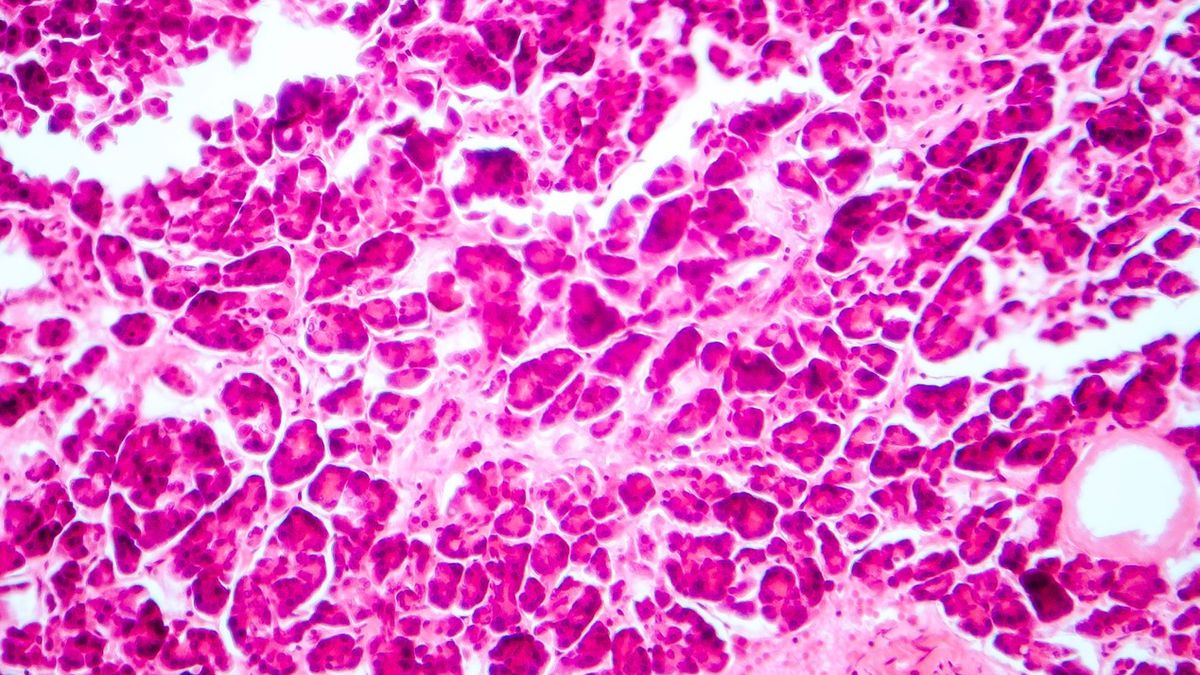

Wysepki Langerhansa, inaczej wyspy trzustkowe, to skupiska komórek pełniących funkcje endokrynne. Są rozrzucone w miąższu trzustki. Wydzielają hormony peptydowe, które odgrywające kluczową rolę w utrzymaniu równowagi gospodarki węglowodanowej. To insulina, proinsulina, peptyd C i amylina, glukagon, somatostatyna oraz polipeptyd trzustkowy. Jaką pełnią rolę? Czym grożą zaburzenia?

Wysepki Langerhansa, inaczej wyspy trzustkowe, nazywane także komórkami trzustki, to jeden z gruczołów wydzielania wewnętrznego. Przyjmuje postać skupisk komórek, które są rozrzucone w miąższu trzustki, głównie w obrębie jej ogona. Zostały odkryte w roku 1869 przez niemieckiego anatoma i patologa Paula Langerhansa.

Budowa i rola wysepek Langerhansa

Wysepki Langerhansa to część wewnątrzwydzielnicza trzustki. Są rozproszone lub tworzą odrębny narząd. Każda ma własne naczynia krwionośne i unerwienie oraz specyficzną strukturę. Składa się z około 2,5 tysiąca wysoko wyspecjalizowanych komórek różnego typu, które wydzielają hormony (takie jak insulina, glukagon czy somatostatyna).

Wyspy trzustkowe Langerhansa stanowią od 1% do 3% masy narządu. W jednej trzustce jest ich około 2 mln. Około 70% puli komórek wysepkowych stanowią komórki beta. Wysepki Langerhansa odgrywają dużą rolę w wydzielaniu dokrewnym. Jest ono regulowane przez sprzężenie jelitowo-trzustkowe, co ma związek z obecnością i trawieniem pokarmu.